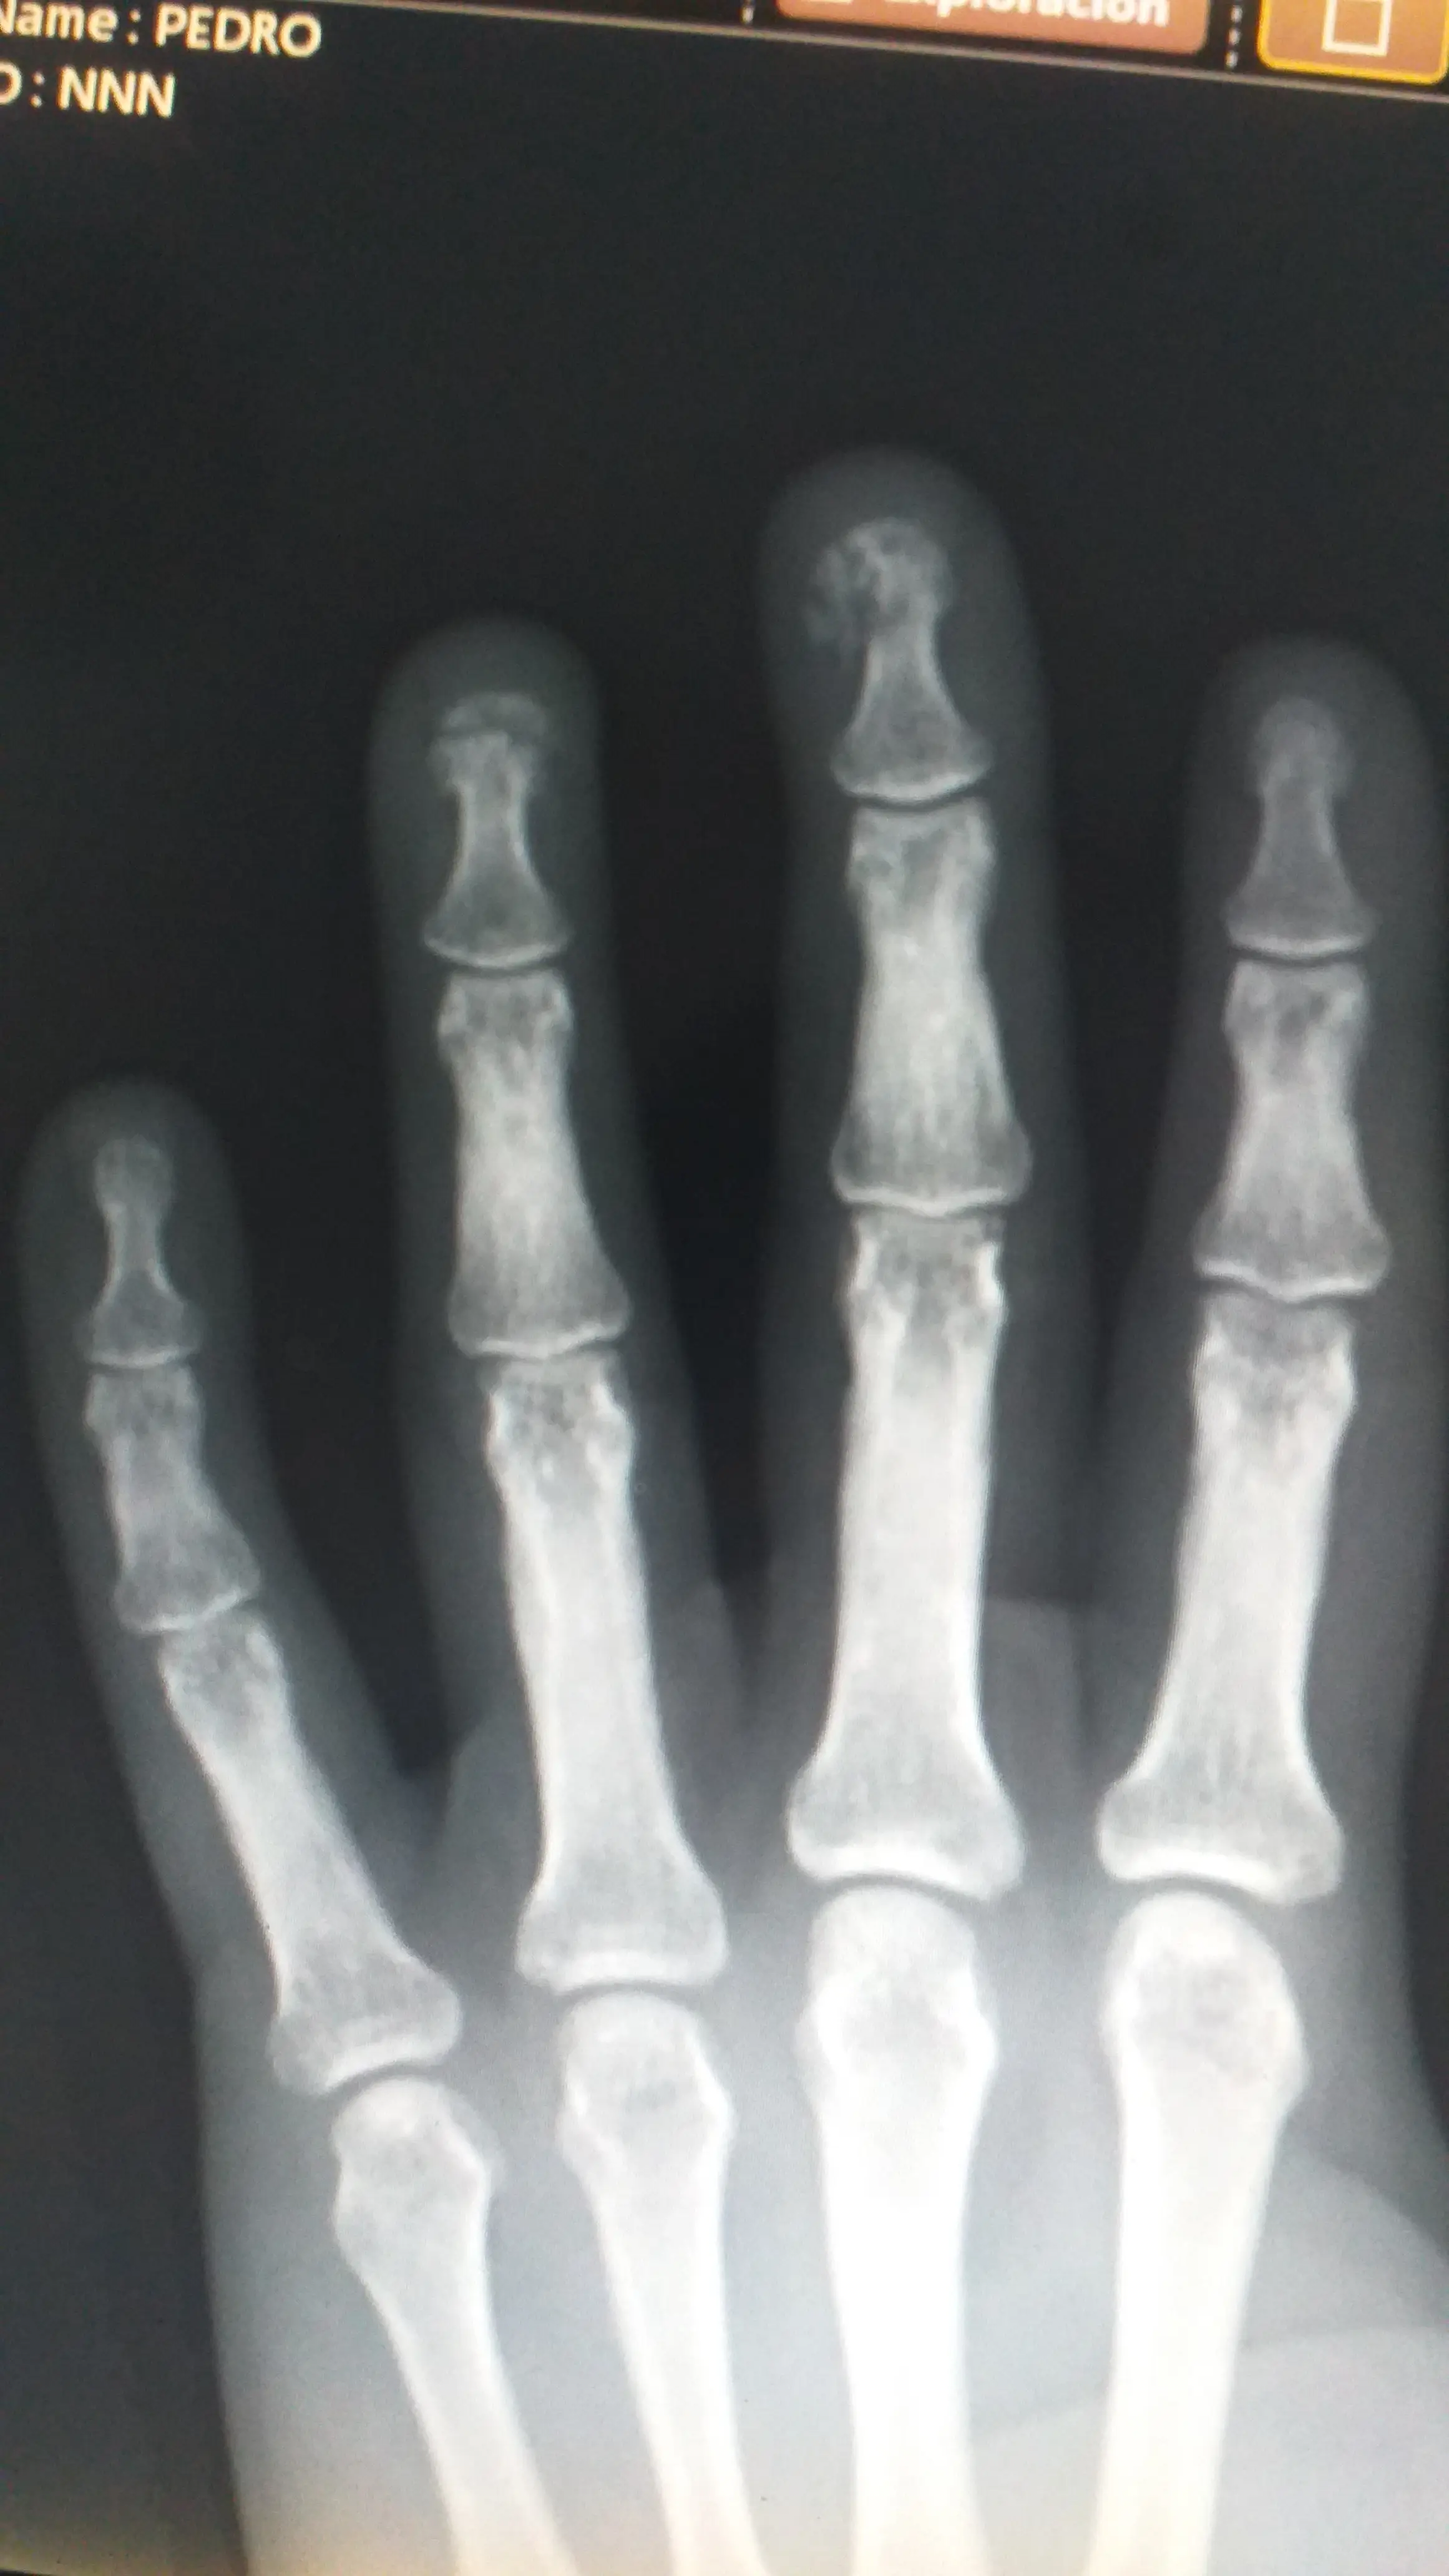

Furou em cima da unha. As duas. Na hora, nem consegui ver o estrago direito de tanta adrenalina. Corri pro hospital com a mão latejando e o pensamento em looping: “como eu fui deixar isso acontecer?” Resultado: antibiótico, anti-inflamatório e uma bela pausa forçada nos projetos. Agora só digito com o indicador esquerdo.

⚠️ Ver raio-x da mão (imagem forte – clique para abrir) Raio-x da mão com lesão